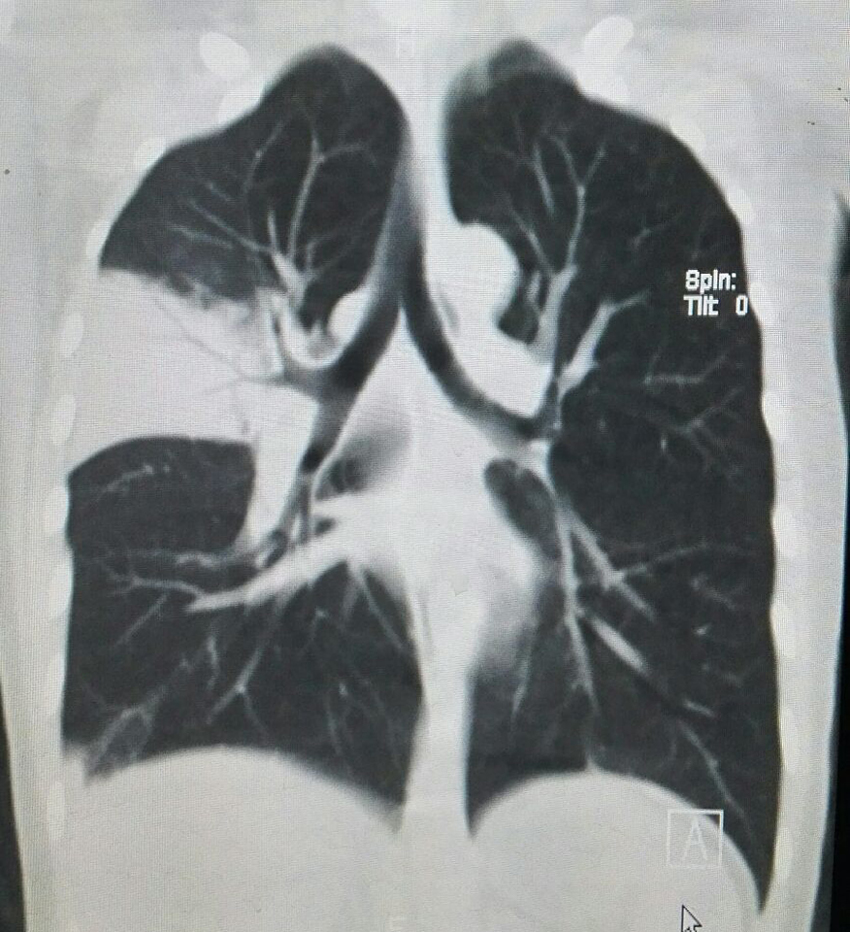

【病例】大叶性肺炎1例CT影像表现

性别:男,年龄:32岁,发热咳嗽,胸痛2天

正确答案是:B、大叶性肺炎;

[影像描述]

CT所见右肺中叶见大片状高密度影,内可见充气支气管征